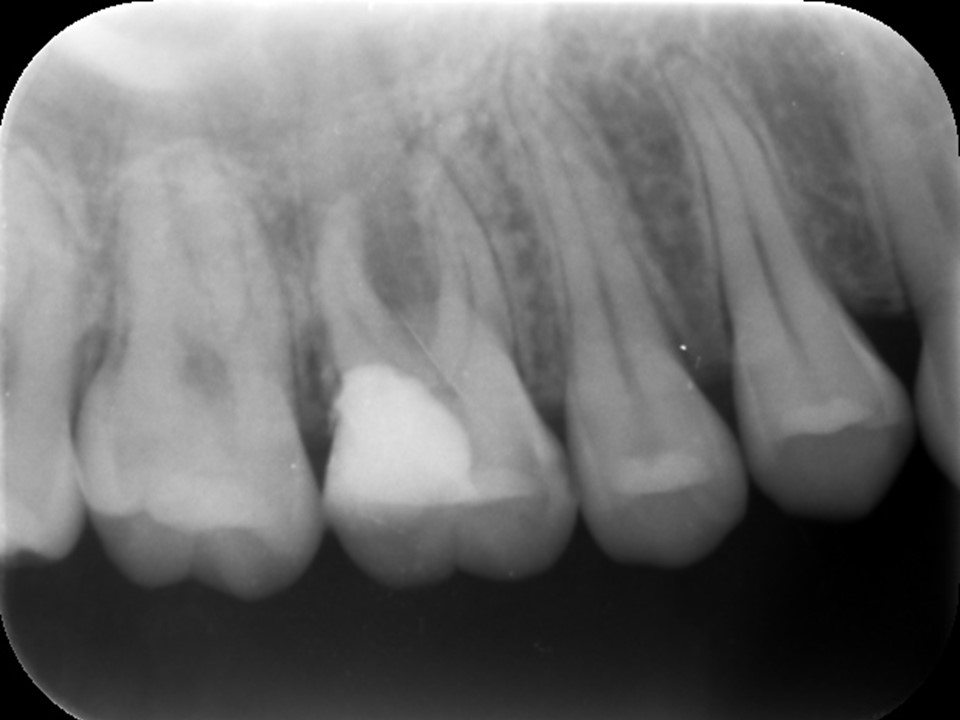

Case2 パーフォレーション(穿孔)

のリペアを行ったケース

診断と治療計画の立案

当該歯のレントゲンおよびCTによる診査にて、根尖部に根尖病巣と思われるX線透過像を認めました。また、歯根の側方には歯の方向を間違えて削った跡があり、パーフォレーション(穿孔、穴)が疑われました(下写真)。

歯髄壊死・歯髄壊疽から生じた慢性化膿性根尖性歯周炎と診断し、感染根管治療を行うことにしました。

パーフォレーションがある場合は、バイオセラミックセメント(MTA,RRMなど)でリペアをする計画としました。

治療前レントゲン | 治療前CT |

![]() |

術前のレントゲンおよびCT画像です。根尖部に根尖病変と思われるX線透過像を認めます(黄矢印)。歯根の側方には、方向を間違えて削ったと思われる跡が見られます。